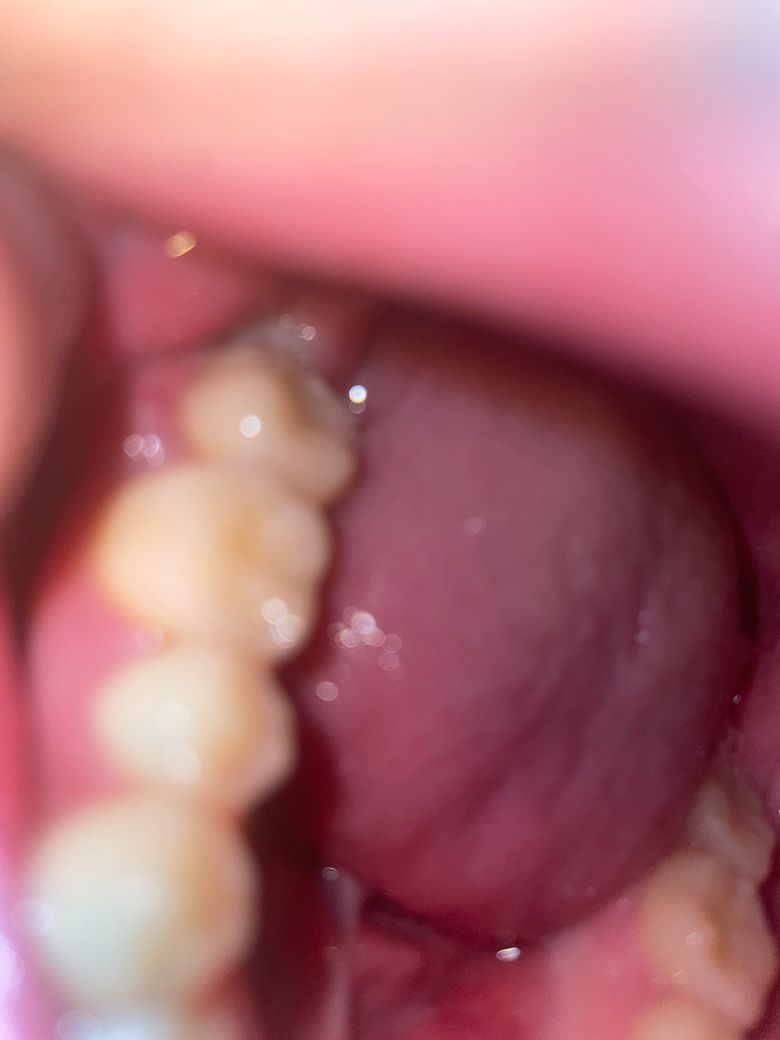

오른쪽 어금니 뒤에 사랑니인가요???? 발치한다면 많이 아플까요

아랫어금니 뒤에 뭐가 보이는데 사랑니 일까요 ㅠㅠ 지금은 통증은 없는데 살짝 이물감이라고 해야 할까요 그런건 있습니다 통증은..살짝 욱신거림? 정도에요 하루빨리 빼야할까요 너무 아플까봐 걱정이 되는데 조금 보이는 사랑니면 안아프다고는 들었습니다..많이 아플까요

• 1번 째 사진

엑스레이 사진을 봐야 정확히 할수 잇겟지만 인제 사랑니가 잇몸을 뚤고 맹출되고 잇는거 같습니다.

현재 사랑니가 나오고 있는 것으로 보이며, 사랑니 방향 및 상태를 확인하기 위해서 치과에서 엑스레이를 찍고 발치 필요여부를 확인하길 권합니다.

만약 기울기가 비뚤어져 있거나 한 경우에는 앞의 어금니를 상하게 할수 있기에 빠른 발치가 필요로 됩니다.

사랑니가 맞는 것으로 보입니다. 빼러 가시면 될 것 같고 크게 아프지 않으니 너무 걱정안하셔도 됩니다.

부분매복사랑니로 보입니다 사랑니가 주변 잇몸 염증, 옆 어금니 충치유발 가능성이 있는 부분매복이므로 발치를 추천드립니다